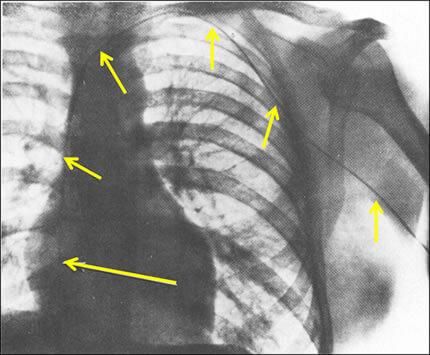

図3

これはカテーテル(尿管用)を人間の心臓の中に入れることができることを証明した世界で最初の写真です(1929年)。

この論文から始まった心臓カテーテル検査に関する研究に対して1956年にノーベル賞が贈られました。

これを撮影し、論文を書いたのはフォルスマンというドイツ人医師です。この写真は自身にカテーテルを挿入して撮影しているのです。

撮影したのは、1929年のことです(医師国家試験に受かったばかりの25歳の時です)。自分の左肘皮膚を切開して(!)肘静脈(ちゅうじょうみゃく)を露出してそこから尿管カテーテルを挿入したのです。

カテーテルを挿入後、歩いてレントゲン透視室に赴いてカテーテルを心臓付近へ誘導して撮影したのが、この図3のレントゲン写真です。

細い管が肘静脈 → 腋窩静脈 → 鎖骨下静脈→ 無名静脈 → 上大静脈 → 右心房を通っているのがお解りになりますでしょうか?自分で麻酔をして皮膚を切開していますが、麻酔をしても痛そうです。